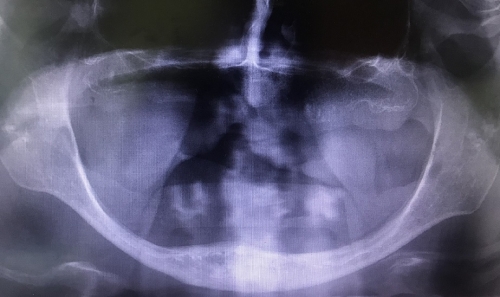

Sogovornik pravi, da so pacienti upravičeni do plačila vstavitve zobnih vsadkov po operaciji v zgornji ali spodnji čeljusti zaradi rakavega obolenja. Prav tako so upravičeni bolniki z oligodontijo oziroma prirojeno odsotnostjo vsaj šestih stalnih zob. Tudi bolnikom s prirojeno anomalijo kosti ali razcepom kosti (shiza) obvezno zavarovanje krijestroške  vstavitev zobnih vsadkov. Najpogostejša indikacija pa je napredovala atrofija – resorpcija kosti zgornje ali spodnje čeljusti. A resorpcija mora po Lekholm-Zarbovi klasifikaciji dosegati stopnjo D ali E (slika 1). V navedenih primerih je oskrba s klasično totalno protezo zaradi slabih anatomskih pogojev nesmiselna, ker ne omogoči ustreznega funkcionalnega rezultata. Število zobnih vsadkov, ki omogočajo izdelavo z vsadki podprte proteze je omejeno na dva v spodnji čeljusti in štiri v zgornji.